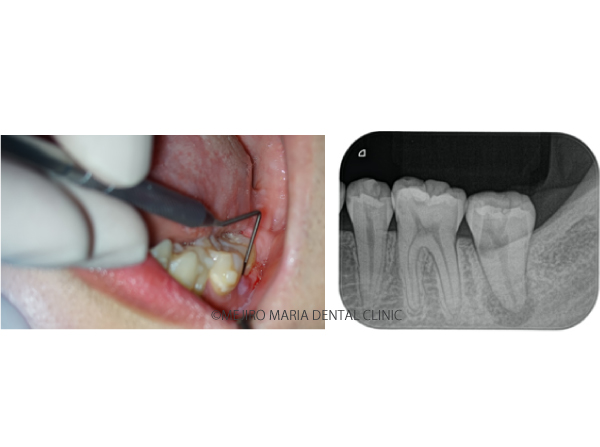

【症例】穿孔修復・パーフォレーションリペア|他院での偶発トラブルに対応したケース